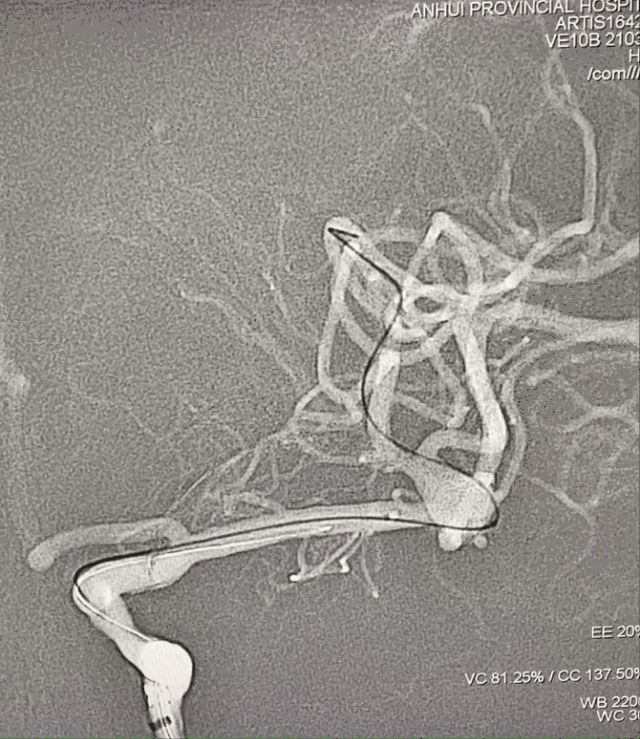

左侧大脑中分叉处(上干)动脉瘤,夹层可能性大;瘤体4.3mm×5.1mm,瘤颈5.8mm。

远近端载瘤动脉直径分别为2.17mm、2.58mm。

超选MCA上干血管,将Accessway支架微导管置入载瘤动脉远端。

调整畅医达(Choydar)FD(2.5×20mm)至合适位置,瘤体内填入少量弹簧圈后支架半释放。

畅医达(Choydar)血流导向装置完全释放。

术后即刻造影提示载瘤动脉通畅,支架打开充分,贴壁良好,瘤体内造影剂滞留明显。